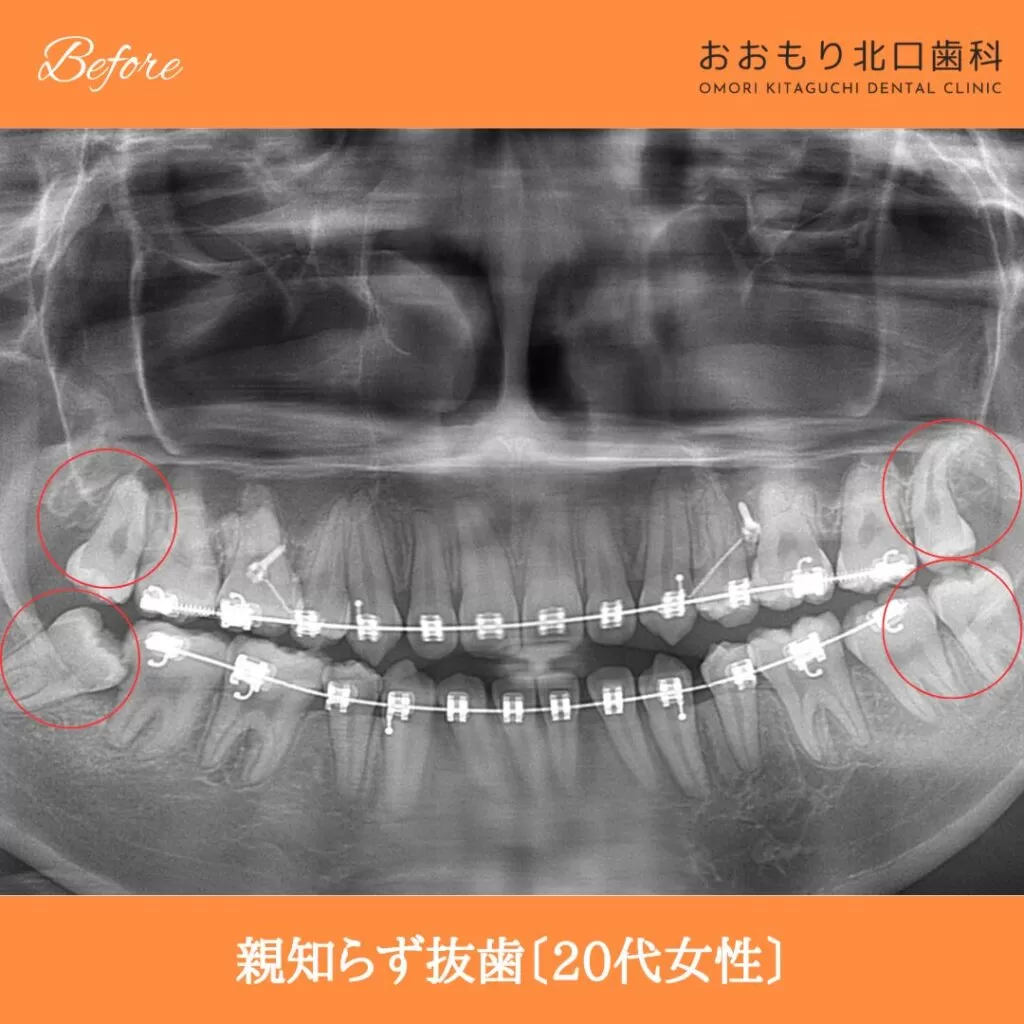

症例紹介㊶親知らず抜歯(20代女性)

本日は「親知らず抜歯」を行われた患者さまのビフォーアフターをご紹介します。

【治療名】親知らず抜歯

【患者さん】20代女性

【リスク】 親知らずの抜歯は、手術中は麻酔により痛みを感じることがほとんどありません。

しかし、麻酔が切れた後には、時には腫れや痛みが発生することがあります。